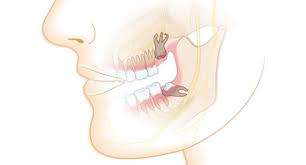

Entzündungen und Spannungsgefühle sind ebenso möglich wie eine Auflösung des Knochens oder die Bildung einer Zyste um den Zahn.

Zudem verschieben sie manchmal benachbarte Zähne. Patient Do 27122020 - 2322 Uhr Hallo mir wurde am 181220 ein Weisheitszahn unten links operativ entfernt. Sie können aber auch zu Schmerzen Schwellungen Karies oder Entzündungen am Zahnfleisch führen. WASS PSASSIERT WEN MAN SICH SEINE WEISHEITSZÄHNE NICHT ZIEHEN LÄSST. Vorab lässt sich sagen dass es in keinem Fall empfehlenswert ist den Durchbruch der Weisheitszähne oder die mit ihm verbundenen Probleme zu ignorieren. Kieferorthopädischer Sicht notwendig werden die Kosten von der Krankenkasse übernommen. Der Schmerz ist nur ein Symptom zu großer Weisheitszähne. Außerdem können Tinnitus Ohrensausen Ohrenschmerzen Kopfschmerzen von den Weisheitszähnen verursacht werden und wenn sie schief wachsen oder der Kiefer nicht genug Platz bietet dann drücken sie auf die anderen Zähne. Daher sollten Sie die Entscheidung einem erfahrenen Zahnarzt anzuvertrauen der nach einer umfassenden Voruntersuchung eine fachkundige Empfehlung geben kann.